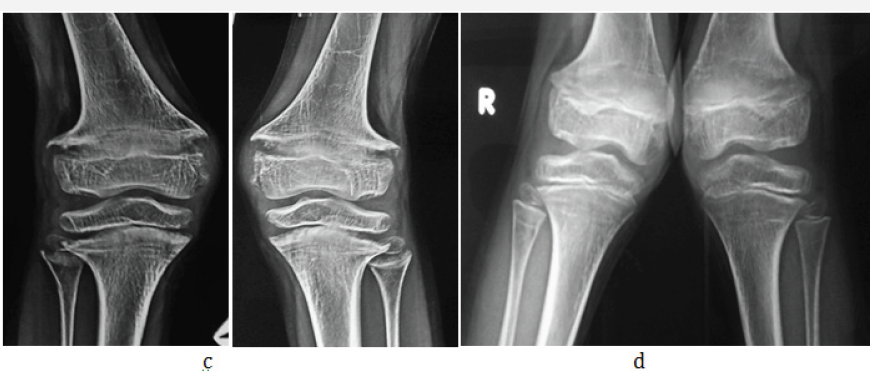

Figure 2 c& d: 1 1/2yrs, Rickets, a- hands, b- knees.

In young children and adolescents, characteristic radiological appearances are noted on conventional films. These include osteoporosis, metaphyseal cupping and ground glass appearance of growing and weight bearing bones (Figure 2a-2d). Rachitic rosary deformity is common in the chest with cupping of the costochondral junctions (Figure 2e & 2f).

Bowing deformities and knock knees are common in the lower extremities (Figure 3a-3c).